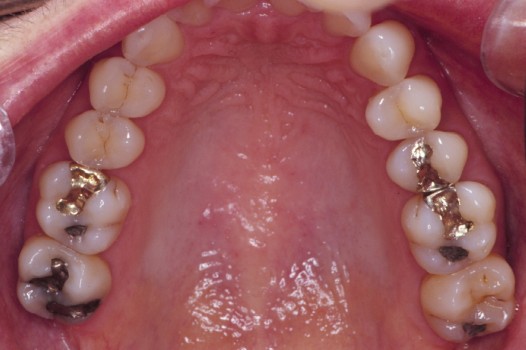

Traditional amalgam (mercury) fillings have been used for over a century, but concerns about health risks, tooth fractures, and long-term decay have led many dentists to adopt modern alternatives. Today, metal-free restorations offer healthier, stronger, and more natural-looking results.

Using advanced resins, ceramics, and state-of-the-art bonding techniques, Dr. Klim can restore teeth with precision, preserving healthy tooth structure while preventing fractures, bacterial invasion, and future toothaches.